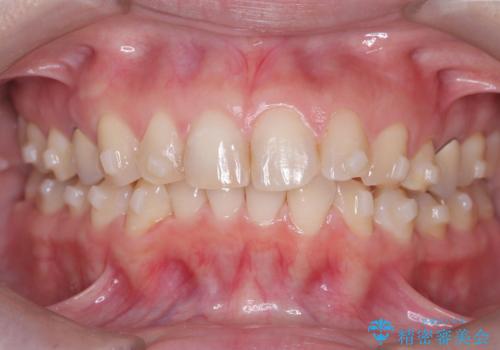

- 下の前歯のデコボコ(叢生)を気にされてご来院されました。精密な検査の結果、下の前歯を並べるスペースが不足していることが判明。患者様のご希望から、透明で目立ちにくい**インビザライン(マウスピース矯正)による治療計画を立案しました。主に歯の側面をわずかに削るIPR(歯間乳頭保護下ストリッピング)**などでスペースを確保し、下の前歯の叢生を解消することを目指します。